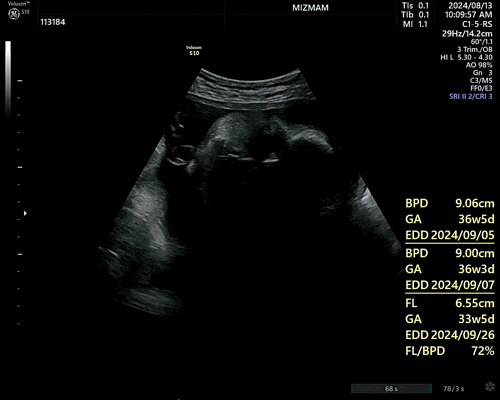

임신일기#9 마지막으로 쓰는 임신일기! (37주차~출산)

37~38주차 이제 정말 마지막달! 마지막달이 정말 힘들다더니 배는 점점 나오고 몸은 점점 무겁고,, 화장실...

임신일기#8 각종 이벤트로 즐거웠다가 슬펐다가,, 다이나믹한 임신막달 (32~36주차)

32주차 드디어 백일해주사맞음! 생각보다 아픈게 오래가서 당황,, 주사맞고 이렇게 뻐근했던 적은 첨이라 3...